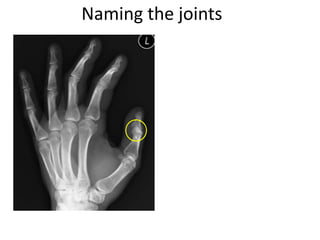

This document provides an overview of hand anatomy including:

- Naming the bones, joints, tendons, nerves and skin landmarks of the hand and wrist.